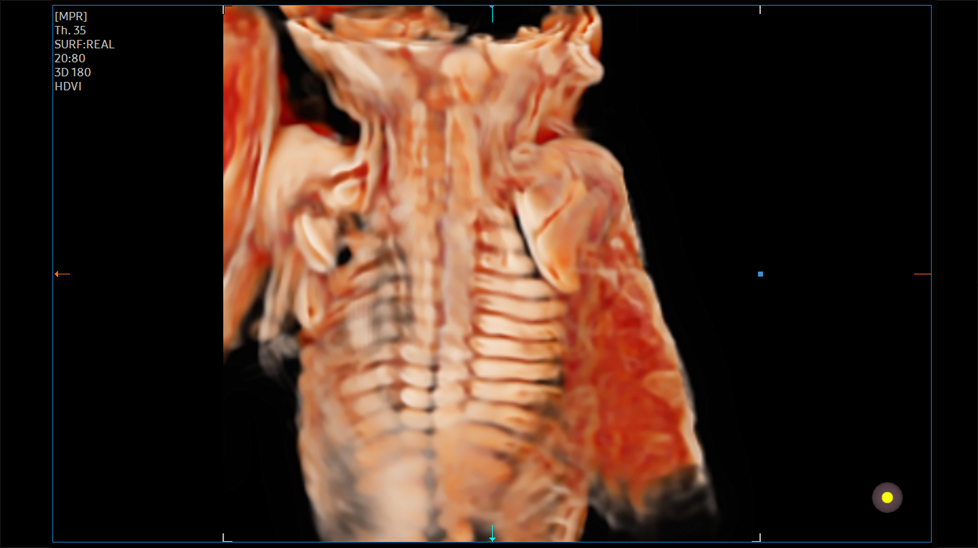

Объемное изображение высокой четкости HDVITM - это технология объемной визуализации, которая улучшает визуализацию краев и небольших структур на объемных данных. Улучшенная выразительность границ и насыщенность изображения позволяют передать самые детали от угла до тени плода.

на изображении: Позвоночник плода с 3D